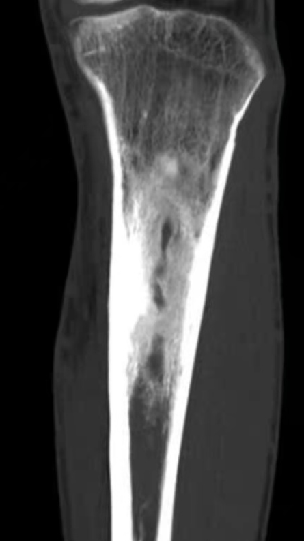

多年来,贵州航天医院各科室紧跟医学前沿,不断强技术、补短板,大力开展新技术、新项目,完成了许多高精尖、高难度、本地区“首例”的技术,填补了医院医疗技术空白,满足了群众日益增长的医疗需求。 贵州航天医院骨科率先在遵义地区开展骨搬移技术,截至目前,已治愈慢性骨髓炎、感染性骨不连、骨缺损、脉管炎、糖尿病足患者200余例,糖尿病足治疗保肢率达到98%。 本期,我们将为大家带来骨科特色技术——骨搬移技术(Ilizarov)。 案例分享 一名59岁的患者,身患糖尿病12年,在来我院3个月前出现了右脚溃烂的症状,来院就诊时,患者的右脚十分红肿,右脚脚趾坏死,伤口处不断流出黑红色脓液,情况十分严重。在接诊到患者时,骨科专家团队高度重视,立刻为患者完善了CT血管造影(CTA)等相关检查,诊断为:2型糖尿病,糖尿病周围血管病变,右糖尿病足。 术 前 考虑到患者情况比较严重,为最大限度保证患者肢体完整,科室专家团队进行了严格的讨论评估,为患者制定了骨搬移技术治疗方案,在征得患者及其家属的同意后,成功通过搬移骨块为患者进行治疗,促进患者病变肢体血管再生。 胫骨横向骨搬移外架固定 清除感染病灶 术后调节外架,通过搬移骨块 促进患肢血管再生 患者在术后三周前来换药,观察到感染得到进一步控制;术后六周复查,患者病变处已愈合,进行CT血管造影(CTA)后可明显观察到足部血管再生。 术后3周 术后6周愈合 CT血管造影见足部血管再生 糖尿病患者全身与局部的问题互为影响,形成恶性循环,糖尿病足溃疡创面迁延不愈,常见干性坏疽、湿性坏疽、趾坏死、深且大的溃疡以及骨髓炎等症状,还可导致脓毒血症,以往为保全生命,患者被迫选择一次或多次截肢。骨搬移技术的发展进步,能在血糖有效控制、局部有效清创下,有效促进患肢微血管再生,改善患肢血供,达到糖尿病足更快治疗康复的目的,并能根据病变情况最大限度的保障患者肢体完整。 什么是骨搬移技术 骨搬移技术是通过使用专用的骨外固定器固定骨段,每天缓慢牵拉,在牵拉搬移过程中,骨段尾部形成新骨及新的软组织,从而修复骨骼缺损及软组织缺损。是治疗大段骨缺损、骨不连、骨感染、肢体畸形的金标准方法,也用于治疗脉管炎、糖尿病足等肢体缺血性疾病。 骨感染缺损 切除感染段 搬移骨段 新骨形成 骨感染根治愈合 骨搬移技术原理 生物组织在持续、稳定、缓慢牵拉下,能刺激细胞分裂、组织再生,骨外固定技术运用该原理,通过持续缓慢调节外固定器形成牵拉张力,促进牵引成骨与相邻组织再生,如神经、血管、肌肉、皮肤等再生,达到治疗大段骨缺损、肢体缺血如糖尿病足等疾病的目的。 骨搬移技术优势 (一)除治疗骨缺损、骨不连外,有更广的适用范围,利用组织再生、血管再生等特性,能大量运用于肢体畸形的矫形、糖尿病足等的治疗。 (二)治疗效果确切,重建肢体外型和功能,极大降低截肢率和残疾率。 (三)明显提高了患者生活质量,极大减轻其家庭及社会负担。 肢体畸形的矫形 慢性骨髓炎 骨段切除 术后1年 濒临截肢的脉管炎术后6周 难愈创面术后3周 贵州航天医院骨科 专家团队 赵学平 骨科主任 主任医师 临床擅长:从事骨科临床工作30余年,对骨科常见疾病的诊治具有丰富的临床经验。 世界中医药联合会脊柱康复专业委员会常务理事,中华中医药学会整脊分会常务委员,中国中西医结合学会骨伤科分会肢体矫形功能重建与康复专家委员会常务委员,中国研究性医院学会骨科创新与转换专业委员会关节外科学组保髋工作委员会常委,中国康复技术转化及发展促进会骨外科与康复技术转化专业委员会常务委员,泛珠三角区域运动医学联盟(PPRD-SMA)理事会常务理事,中国研究型医院学会运动医学专业委员会委员,贵州省中医药学会整脊分会副主任委员,贵州省中西医结合学会银质针专业委员会副主任委员,贵州省康复医学会骨与关节专业委员会常务委员,贵州省人民医院骨科专科联盟常务理事,贵州省康复医学会骨内科专业委员会常务委员,中华医学会贵州省骨科学会委员,贵州省康复医学会脊柱脊髓专业委员会常务委员,贵州省运动医学分会委员,贵州省康复医学会骨与软组织肿瘤专业委员会委员,遵义市医学会创伤分会副主任委员,贵州省康复医学会骨内科专业委员会遵义地区分会常务委员,遵义市医疗事故鉴定、伤残鉴定、工伤鉴定、司法鉴定专家。 长期从事骨科临床研究及教学工作,在国家级、省部级杂志发表论文20余篇,SCI论文2篇,参与主编骨科专著2部,主持省部级科研项目2项,参与指导省部级、市级科研项目6项。 陈明勇 骨科副主任 副主任医师 临床擅长:从事创伤骨科工作约20年,对骨缺损、骨不连、骨肿瘤、肢体畸形等的肢体矫形重建及功能重建,慢性化脓性骨髓炎的根治治疗、糖尿病足的保肢治疗、快速康复理念(ERAS)下的老年骨折的诊治,四肢复杂骨折的诊治,四肢骨折等微创手术治疗具有丰富的临床经验。 2004年毕业于遵义医学院临床专业,曾在中国人民解放军总医院、广西医科大学第一附属医院、上海第六人民医院骨科进修。中国中西医结合学会骨伤科专业委员会横向骨搬移治疗糖尿病足及微血管网再生学组首届委员,遵义市医学会创伤分会常务委员。 瞿 辉 骨科 副主任医师 临床擅长:对骨科的常见病、关节外科、脊柱外科及运动医学疾病的诊治具有丰富的临床经验,熟练掌握骨科手术操作技术。 毕业于遵义医学院临床医学系,2005年前往广州中山大学第一附院骨显微医学部进修学习,2011年前往成都华西医院进修学习,并多次在省内外学习骨科相关知识,是中华医学会骨科分会会员。 赵兴东 骨科 主任医师 临床擅长:擅长骨科的常见病及各种创伤、四肢骨折创伤修复、骨感染、手足疾病的诊治和手足体表畸形的矫形整复,熟练掌握骨科四肢骨病及创伤的手术操作技术,尤其在四肢关节复杂性损伤、手足外伤、组织缺损创面、难治创面的皮瓣修复方面及平足、高弓足矫形方面及四肢慢性疼痛诊治、康复方面具有丰富的临床经验。 硕士研究生,毕业于遵义医学院临床外科系,2015年前往山东省立医院手足外科进修学习;遵义市医学分会创伤分会第一、二届委员,遵义市手外科医学会第二委届员会常务委员;在省级及省级以上期刊发表文章9篇,参编著作2部,参与主持并完成市级课题1项,参与市级课题2项、省级课题1项。 张俊凯 骨科 副主任医师 临床擅长:从事骨科临床工作28年,对创伤骨折、骨感染、骨缺损、骨不连等外科诊治,四肢骨折的微创手术治疗,四肢复杂骨折(如关节内粉碎性骨折、多发骨折等)的损伤控制及手术治疗等具有丰富的临床经验。 1995年毕业于遵义医学院临床专业,2009年前往复旦大学附属医院骨科进修1年。 卢懿明 骨科 副主任医师 临床擅长:从事骨科工作18年,对创伤骨折、四肢骨折的微创手术治疗、四肢复杂骨折(如关节内粉碎性骨折、多发骨折等)的损伤控制及手术治疗,尤其是髋部骨折的PFNA等微创技术,踝关节骨折、膝关节周围骨折的Mipo微创技术等具有丰富的临床经验,开展了4项新技术,发明6项新型专利技术。 2005年毕业于遵义医学院临床专业,2017年,前往南方医科大学第三附属医院骨科进修半年,回院后运用Mipo技术对骨干骨折及干骺端骨折的治疗技术,同时积极开展骨盆骨折、髋臼骨折腹直肌外侧切口的应用;发表了多篇专业论文,经常参与省内外学术交流会授课,获得医院荣誉称号多个。 邬夏荣 骨科 副主任医师 临床擅长:从事骨科工作16年,对四肢复杂骨折、骨肿瘤的诊治,尤其是足踝创伤、慢性踝关节损伤、平足症等诊疗具有丰富的临床经验。 2006年毕业于遵义医科大学临床医学专业,曾在陆军军医大学西南医院进修学习,发表多篇骨科学术论文。 余德怀 骨科 副主任医师 临床擅长:从事骨科工作10余年,对运动医学、骨关节、脊柱外科常见病、多发病的诊治具有丰富的临床经验。 硕士研究生,2011年毕业于遵义医学院临床医学专业,曾前往遵义医科大学附属医院运动医学专业进修学习;是贵州省医学会运动医学分会青年委员,西部关节镜联盟委员;发表多篇骨科学术论文。 冯 乾 骨科 副主任医师 临床擅长:从事骨科工作近20年,熟练掌握骨科多发病及常见病的诊治,尤其对脊柱退变性疾病的诊断及治疗具有丰富的临床经验,主要研究脊柱微创相关治疗方式,能熟练开展椎间孔镜及VBE。 曾前往北京大学第三医院进修学习疼痛及椎间孔镜、首都医科大学友谊医院专业进修脊柱内镜;是贵州省康复医学会第三届脊柱脊髓专业委员会委员;发明专利3项、发表脊柱外科专业论文多篇。 张艳金 骨科 副主任医师 临床擅长:从事骨外科工作16年,对复合伤、多发伤的救治、四肢骨干骨折、关节周围骨折、骨肿瘤、骨髓炎等诊治具有丰富的临床经验。 中共党员,硕士研究生,2006年本科毕业于山西医科大学第二临床医学院,2011年研究生毕业于北京军区总医院;在“老年COPD患者合并髋部骨折的诊治”国际合作课题组研究两年,在老年髋部骨折的诊治方面具有丰富的经验,并发表论文6篇;承担遵义市级课题1项;承担遵义医科大学的临床教学工作,获得遵义医科大学优秀带教老师荣誉。编撰有《骨科疾病诊疗精粹》一书,开展2项新技术,编撰地方规范《务川自治县创伤骨科常见疾病诊疗规范》一书。 赵小锋 骨科 副主任医师 临床擅长:从事骨科临床工作11年,对骨科常见病、多发病诊疗有较为丰富的临床经验,擅长脊柱相关疾病诊断及治疗,尤其是颈、腰、腿疼痛疾病诊断及治疗,擅长胸腰椎骨折微创经皮穿刺内固定术、经皮穿刺椎体成形术、经皮穿刺脊柱内镜下腰椎间盘摘除术、单纯开创腰椎间盘摘除术、腰椎滑脱复位椎间植骨椎融合内固定术、腰椎管狭窄减压融合内固定术及人工髋、膝关节置换术等。 2012年毕业于遵义医学院外科学专业硕士研究生,2019年参加“遵义市115医学人才精英计划”于上海交通大学第一附属医院培训学习,2023年于北京大学第三人民医院脊柱外科进修学习,曾获得遵义市优秀医师荣誉称号。 遵义市手外科第一届委员,遵义市医学会创伤分会第一届委员,遵义市医学会创伤分会第二届委员,贵州省康复医学会第三届脊柱脊髓专业会委员,遵义市医学会烧伤与整形外科学分会委员,发表论文5篇,其中国家级核心期刊1篇,SCI论文1篇,主持市级课题1项并结题,参与市级课题2项。 贵州航天医院骨科简介 基本情况 贵州航天医院(原3417医院)骨科组建于1968年,前身是以创伤和断肢(断指)再植闻名于世的上海市第六人民医院骨科,中国断肢(断指)再植的奠基者、中科院院士陈仲伟等著名专家、学者多次莅临科室指导医疗、教,是贵州省最早拥有专业骨科技术科室之一,在70年代开展了贵州省首例断肢(断指)再植手术。组建50余年来,诊治患者已逾百万,挽救了无数的伤病员,成为了保障遵义地区人民群众健康的重要支撑。 经过几代人的不懈努力,今天的骨科,已由创伤骨科发展至骨病、骨肿瘤、骨结核等领域,现有脊柱外科、关节外科、四肢创伤、手足外科四个亚专科,成为了集医疗、教学、科研于一体的综合学科,是贵州省临床重点专科、遵义市临床重点专科、遵义市骨科临床医学中心、遵义市基层骨科专科联盟理事长单位。 科室目前开放床位110张,共有医护人员50余人,副高级以上专家18人,硕士研究生15人。拥有一流骨科医疗设备多台,每年不定期选派优秀技术骨干到全国各大知名医学院校进修、学习、参观、交流,并邀请国内、国外知名专家教授来院进行交流、指导,通过不断引进国内外先进的诊疗技术,科室医疗技术水平稳步提升,为广大人民群众提供了优质的医疗服务。 专科特色 骨一科 (一)骨缺损、骨不连的肢体与功能重建 胫骨横向骨搬移技术治疗糖尿病足: (二)慢性骨髓炎的根治治疗 (三)肢体缺血性疾病如糖尿病足、脉管炎的保肢治疗 (四)皮瓣修复 (五)复杂创伤的治疗 (六)老年髋部骨折及小儿骨折快速手术 老年髋部骨折: 骨二科 (一)胸腰椎骨折微创经皮椎弓根螺钉固定术 (二)老年性骨质疏松性患者腰椎滑脱脊柱内固定术(骨水泥螺钉) (三)V形双通道脊柱内镜技术(VBE)腰椎融合术治疗腰椎退行性疾病 (四)老年性骨质疏松性骨折(PVP/PKP)术 (五)人工髋关节置换术 (六)双侧股骨头坏死人工全髋关节置换 (七)右侧全髋置换术后假体周围骨折翻修 (八)人工膝关节置换术 (九)人工膝关节假体松动翻修 (十)关节镜技术 传统手术切口 关节镜技术切口 诊疗范围 骨一科 1.四肢创伤、矫形。 2.手、足踝外科。 骨二科